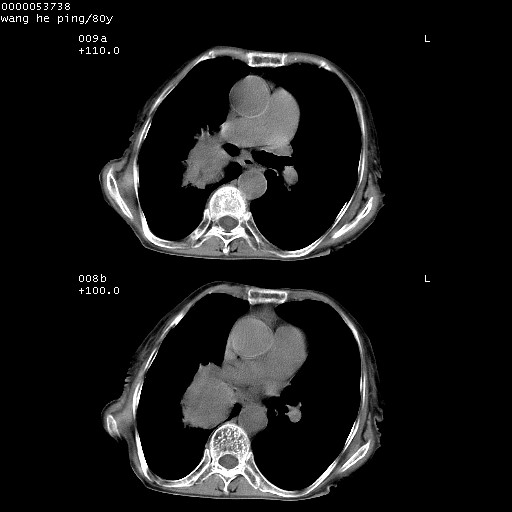

以下是引用黑白光影在2008-8-28 22:33:00的发言:[br]右肺中央型肺癌伴阻塞性肺炎,肺癌肺转移。

以下是引用lshx在2008-8-28 22:06:00的发言:[br]1.右肺中心型肺癌伴阻塞性肺炎,不除外双 肺早期转移。[br]2.心包积液。

以下是引用随光逐影在2008-8-29 7:40:00的发言:[br]1)右肺中心型肺癌伴阻塞性肺炎,肺内转移。2)心包积液(少量)。

以下是引用wqs571018在2008-8-28 21:56:00的发言:[br]右肺中心型肺癌伴阻塞性肺炎可能。

以下是引用liuyue在2008-8-28 22:46:00的发言:[br]1.右肺中心型肺癌伴阻塞性肺炎。[br]2.心包积液(少量)。